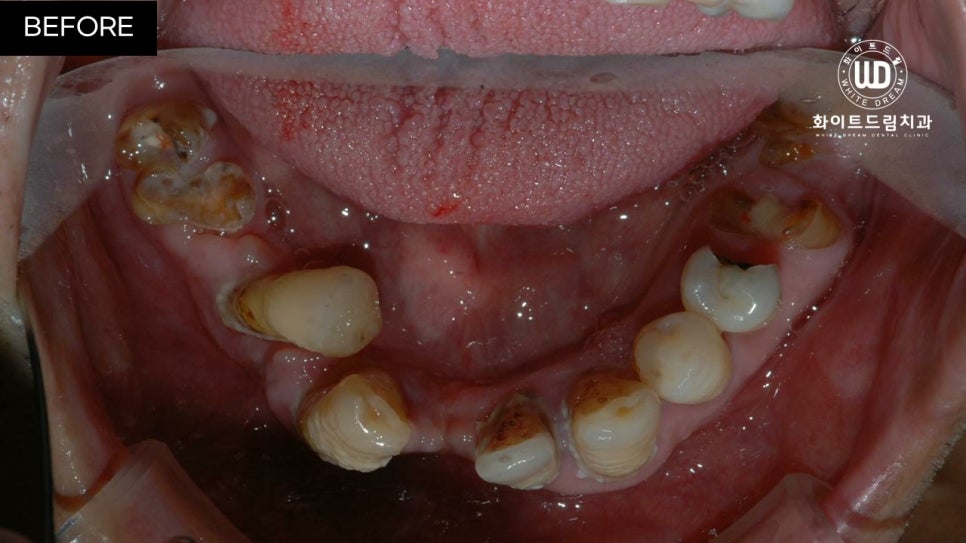

임플란트 식립 전 상, 하악 모습입니다.

육안으로 보이실지 모르겠으나 잔존한 치아 주위염이 심한 상태셨는데요. 뿐만 아니라 치아 파절과 함께 영구치의 뿌리 대부분이 손상되어 있는 상태였습니다.

이미 발치되어 있는 쪽은 치아가 소실된지 오랜 시간이 지나 잇몸뼈가 부족한 상태였고, 현 상태로는 픽스쳐를 식립할 수 없어 전체 발치 후 상악 양측 구치부 상악동 거상술 및 전체 치조골 이식을 동반한 전체 임플란트 식립을 진행하기로 했습니다.